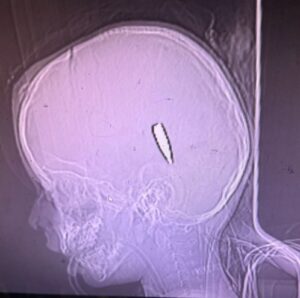

„Guardian sdílel popisy a snímky střelných zranění osmi dětí s vojenskými experty a soudními experty. Řekli, že je obtížné přesvědčivě určit okolnosti střelby pouze na základě popisů a fotografií, ačkoli v některých případech byli schopni identifikovat munici používanou izraelskou armádou.